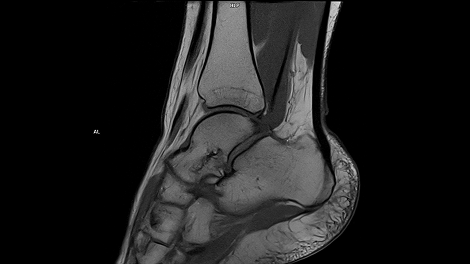

Whether it is head, neck, spine, abdomen or MSK – our clinical experts have complete confidence in the ability of MAGNETOM Free.Max to deliver excellent diagnostic quality for all these standard clinical MRI applications.